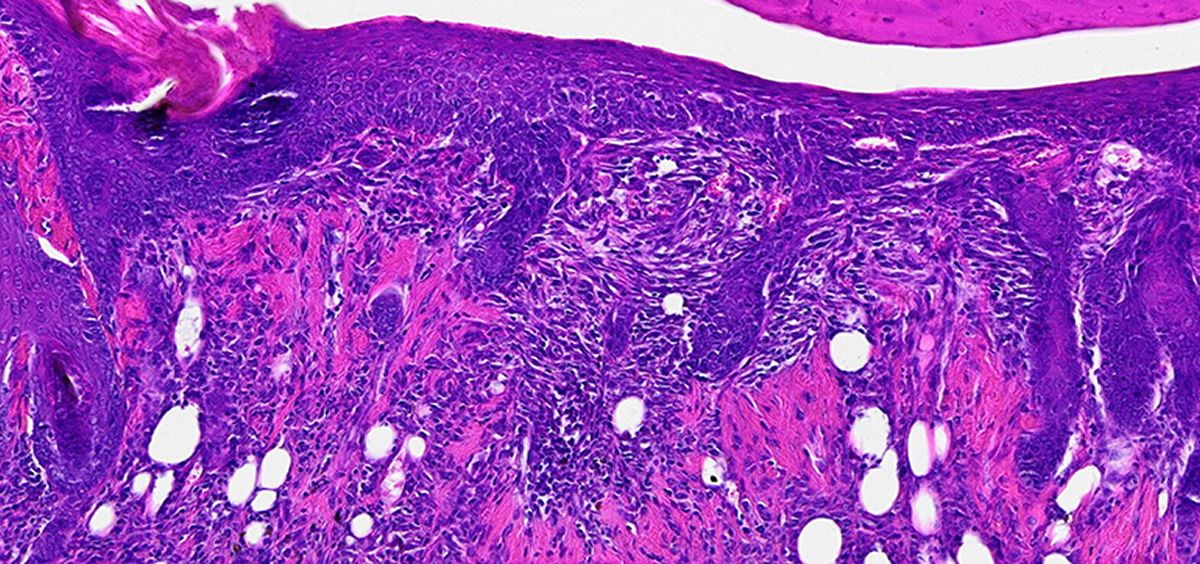

Debido a la intrincada estructura a nano escala de las fibras y micelas, el material parece ser un buen anfitrión para promover el crecimiento celular

Además, debido a la intrincada estructura a nano escala de las fibras y micelas, el material parece ser un buen anfitrión para promover el crecimiento celular.